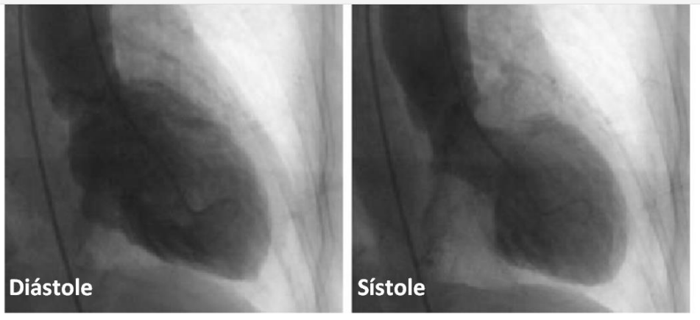

Mulher de 60 anos com HAS e DM tipo 2, relata dor torácica retroesternal em aperto de início há 90 minutos, associada à dispneia, que

começou logo após ser informada do falecimento de seu irmão.

Ao exame: taquidispneica em ar ambiente, sudoreica, corada, acianótica. FC: 120 bpm; PA: 118x64 mmHg. MVUA com crepitação nos 1/3

inferiores bilateralmente. Ritmo cardíaca regular em 3 tempos (B3), bulhas normofonéticas, sem sopros ou turgência jugular patológica a

90º

. O restante do exame físico foi normal.

O eletrocardiograma de admissão encontra-se abaixo e a primeira aferição de troponina ultrassensível foi positiva.

Assinale a opção que apresenta o diagnóstico mais provável.